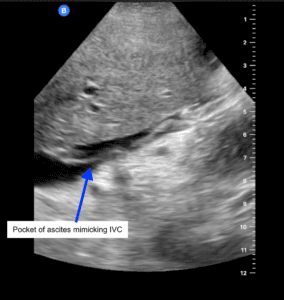

Of patients with severe congestion, one had received a kidney from a living donor with no history of cardiac disease. Severe venous congestion was found on the first day, with both the PV and HV involved without impairment of IRVD. The patient developed polyuria and both venous ultrasound evaluation and renal function normalized in the following days. The second case was a patient with a history of heart failure with reduced systolic function (EF 38%) who received a kidney from a cadaveric donor. On the second evaluation (Day 3), the patient developed severe venous congestion with HV, PV and IRVD involvement sustained for some days, with mild pulmonary congestion. During the first week, his urine output ranged between 1000-2000 mL/day and required only one hemodialysis session due to high uremia. The clinical assessment by the attending physicians always showed normovolemia and the weight gain was 10% as compared to the initial weight. The patient developed heart failure on Day 10 after transplant with signs of low cardiac output. He needed hemodialysis, vasopressors and respiratory support. He even tolerated 5% less under the dry weight reported on admission (Figure1).